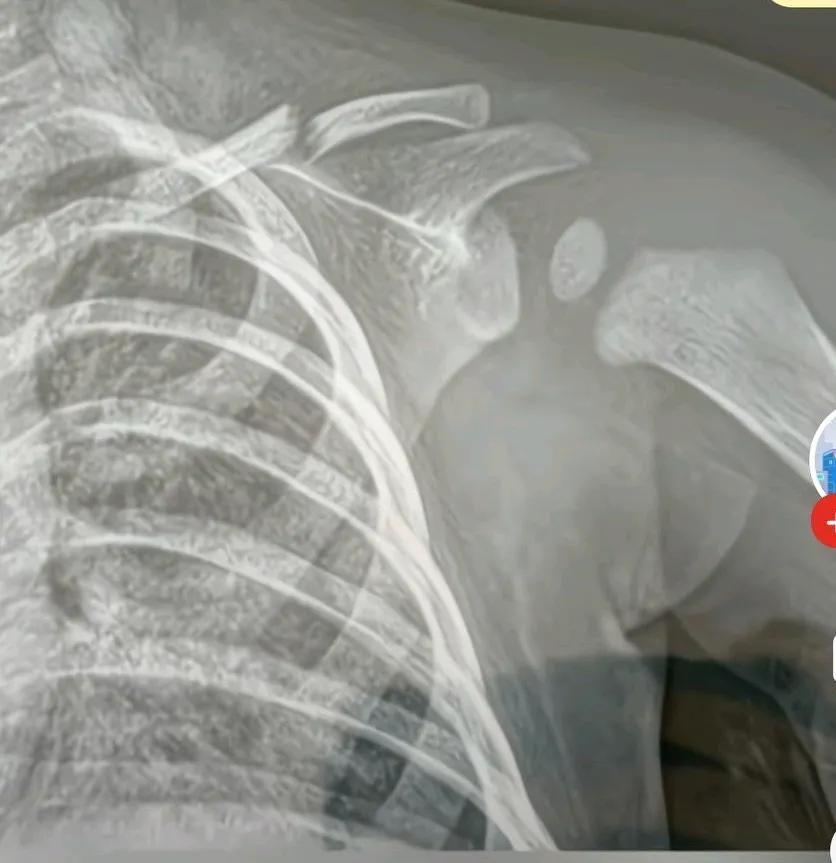

爸爸抱七个多月大的宝宝不慎将孩子跌落,不到半米高的高度,竟将孩子锁骨骨折,医生称孩子太小,无法手术,只能让其自然痊愈, 这爸爸到底会抱孩子吗? 不会抱就不要抱, 抱了孩子还伤害了他。 网友说,这要是女的把孩子摔这样, 这男的说不上怎么叭叭呢, 妈妈还是很不错的, 跑过来没有埋怨爸爸, 只是询问宝宝的状况, 这么大的个男人, 抱个小孩都抱不起, 有什么用处, 早点丢垃圾桶去。